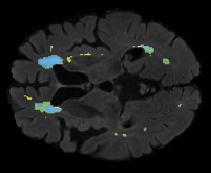

We evaluated our method in segmenting WMH from T1-w images using: a) Synthesized FLAIR images by treating the synthesis as a preprocessing step – we will refer to this method as offline synthesis; b) Synthesized FLAIR images using the proposed method, and c) without any synthesis – we will refer to this method as Unimodal. Baseline methods are illustrated in Figure 2

Table 2: Segmentation results for all proposed methods, each column represent a different slide in the image, blue areas are regions which were correctly labeled, false positives are shown in green, and false negatives in yellow

In order to better understand the above results, we visually analyzed the output segmentation performed for each method. Table 2 shows the results for three different slices (one slice per column). As illustrated, the proposed method is able to produce less false positives. It is also important to note that, unimodal segmentation is the one that produces more false positives, showing the advantage of using synthetic data. Regarding the nature of false positives, it can be easy to see in the third column a large number of false positives are on the border of periventricular lesions for the Unimodal method in comparison to the proposed method. Also from the first and second column, it can be observed that Unimodal tend to produce more small regions of false positives near to cortical areas. Removing such false positives requires additional post-processing steps, therefore, it is of value avoid this kind of over-segmentation. It can also be noted that synthesis methods tend to produce the same kind of false negatives, this may be due to the blurring effects in synthesized images since the information available during testing is limited – which otherwise is available from a FLAIR sequence.